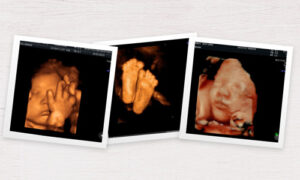

Les innovacions tècniques, mèdiques i d’investigació avancen ràpidament, i les proves mèdiques es realitzen amb equips d’última generació i amb la tecnologia més avançada. Dexeus dona realitza proves diagnòstiques d’estudi en profunditat com la discriminació de tumors benignes / malignes i utilitzen sistemes de IA per la detecció precoç del càncer de mama en imatge mèdica. A més, la seva última innovació és l’ecografia en 4D en temps real amb unes ulleres de realitat virtual. Tota aquesta tecnologia genera gran quantitat d’informació i emmagatzema imatges i vídeos d’alta resolució que els metges especialistes i els seus equips necessiten visualitzar i analitzar amb rapidesa pels seus diagnòstics.